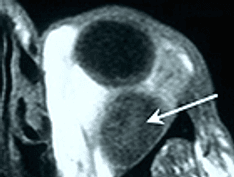

Parenchymal nodularities.